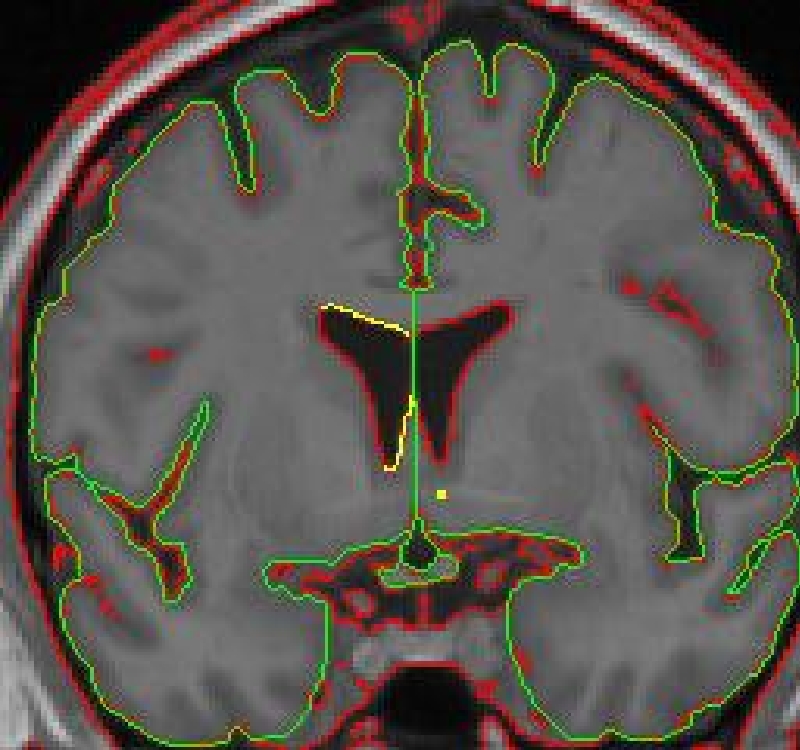

When the caudate is present two histograms are needed to define the two different

borders of the ventricle.

5. You may need to manually connect your "saved" contour to the new

contour. By convention, in cases in which the caudate is present, include the

most inferior extent of the CSF/white matter border as the lateral ventricle

border, even if that necessitates drawing a short line from it to the CSF/gray matter

border.